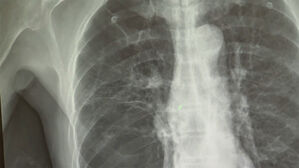

담배 안 피우는데 폐암?…"만성 폐질환 있으면 폐암 위험 3배" ▲ 폐암 X-RAY담배를 전혀 피우지 않더라도 만성 폐 질환을 앓았던 병력이 있다면 폐암 발병 위험이 3배 가까이 높아진다는 연구 결… SBS 2026.02.11 14:19